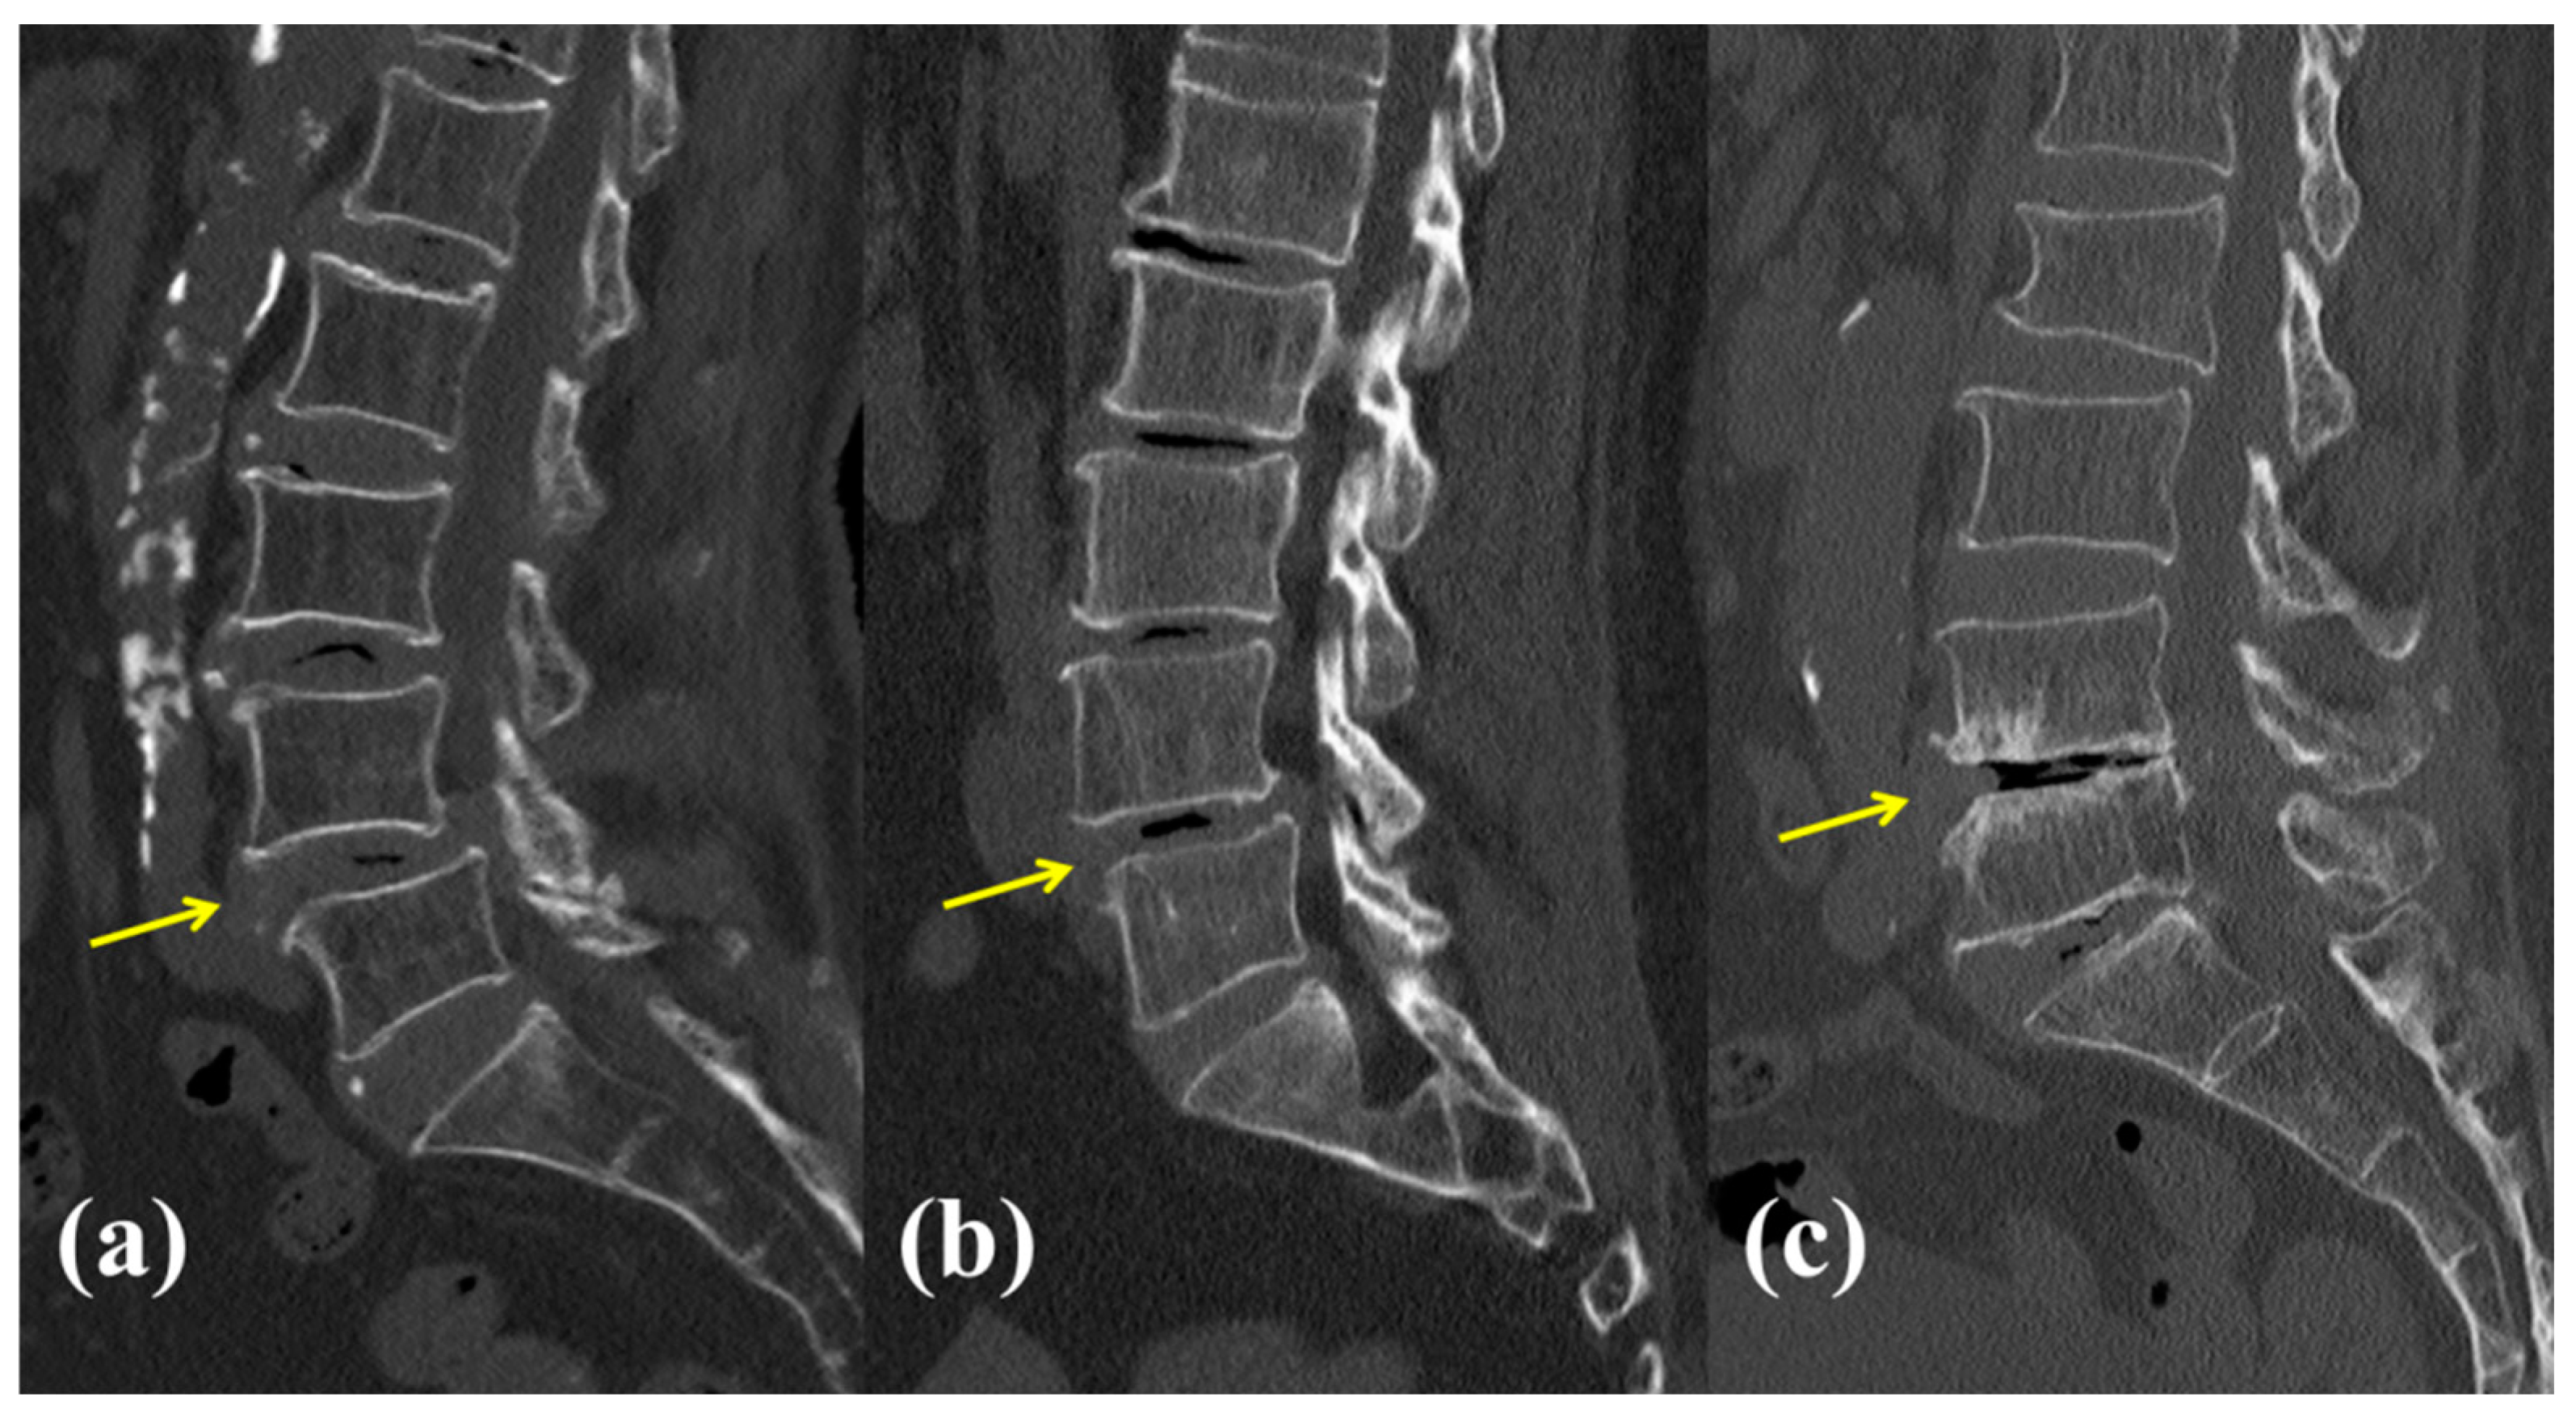

2.3. Data Collection and Radiologic Assessments